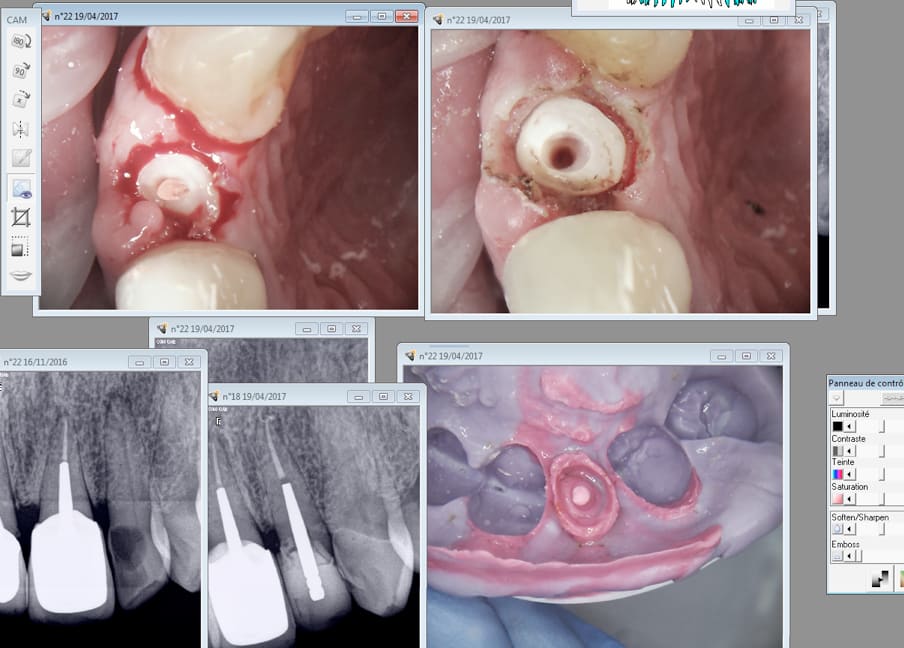

fistule 69

Non il n'y a pas de laser sur le cas précédent. Juste de l'expasyl. -)

Sur celui ci il y a laser.

Ici il y a un chouille de laser en distal.